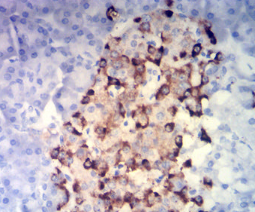

CHGA Mouse Monoclonal antibody[5H10]

The protein encoded by this gene is a member of the chromogranin/secretogranin family of neuroendocrine secretory proteins. It is found in secretory vesicles of neurons and endocrine cells. This gene product is a precursor to three biologically active peptides; vasostatin, pancreastatin, and parastatin. These peptides act as autocrine or paracrine negative modulators of the neuroendocrine system. Two other peptides, catestatin and chromofungin, have antimicrobial activity and antifungal activity, respectively. Two transcript variants encoding different isoforms have been found for this gene.

Immunogen:    Purified recombinant fragment of human CHGA (AA: 278-457) expressed in E. Coli.

IHC    1/200-1/1000